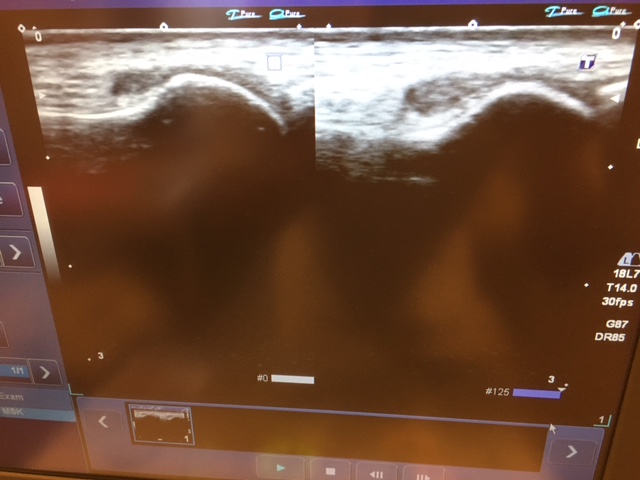

次にエコーです。

基本的には、

圧痛部位を、左右と比較します!

左が患側 右が健側です。

どうですか?

骨の大きさの違い一目でわかります。

左のほうが大きくなってます。